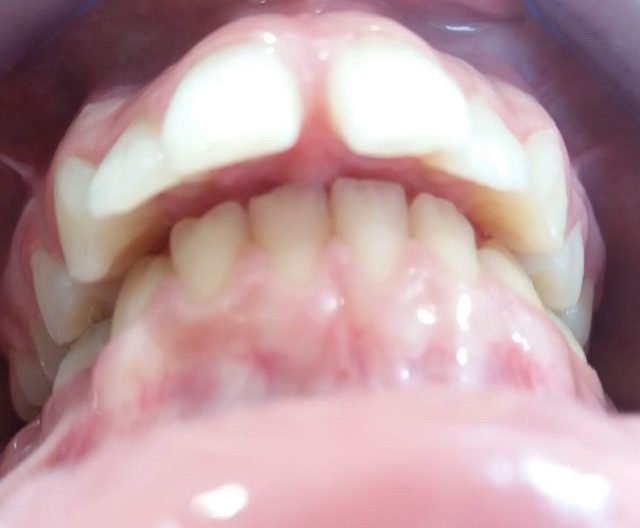

Vamos a ver el tratamiento de ortodoncia de un paciente de 11 años de edad en el que se observa una clase II de tipo dento-alveolar. Tiene un perfil de ligera protrusión del maxilar superior y retrusión de la mandíbula. Los incisivos inferiores llegan a contactar con el paladar superior pero muy hacia atrás. Esto le da un perfil de pájaro. Siendo la causa diversa en las que se mezcla diferentes parafunciones como interposición del labio inferior entre los dientes incisivos superiores e inferiores, o también interposición lingual al tragar etc. Es decir son los músculos (labio, lengua etc.) con sus malos hábitos los que producen las mal oclusiones e incluso trastornos del desarrollo óseo maxilomandibular normal. Es decir los músculos de la cara son los arquitectos de los huesos faciales, en este caso que exponemos para mal.

El tratamiento que se propone es alineamiento dental y estimular un desarrollo o crecimiento mandibular con algo que estimule dicho crecimiento. Este “algo” son los “aparatos funcionales” que actúan como si fueran poderosos músculos que tienden a empujar o estirar (según se diseñe) las estructuras dento-óseas de forma que estimula su crecimiento, siendo, que por su edad, está en época de máximo crecimiento. La mandíbula es un hueso capaz de crecer hasta los 25 años si se la estimula correctamente. Este aparato funcional es una especie de “jumper” o “saltador” o “empujador” que empuja el maxilar superior hacia atrás y empuja la mandíbula hacia delante aprovechando la fuerza de cierre de la arcada dental. Se lleva durante seis meses más o menos y el paciente no se lo puede quitar, es por esto que en realidad funciona tan rápido.